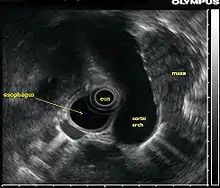

La ecografía endoscópica o ecoendoscopia es un procedimiento en el que se combina la técnica de endoscopia con el uso de ultrasonidos, obteniendo de esta forma imágenes de gran calidad de los órganos internos, sobre todo del esófago, estómago, páncreas y mediastino.[1] Si se combina esta técnica con la ecografía Doppler, los vasos sanguíneos cercanos a estas estructuras también pueden ser evaluados.

Para la realización de la ecografía endoscópica del tracto digestivo superior, se inserta una sonda en el esófago que luego pasa por el estómago y luego por el duodeno durante un procedimiento llamado esofagogastroduodenoscopia. Este procedimiento se realiza para la detección del cáncer de páncreas, cáncer de esófago y cáncer gástrico, así como tumores benignos del tracto gastrointestinal superior. Por otro lado, mediante la inserción de una aguja a través del revestimiento de los órganos a estudiar, permite la caracterización de la biopsia que se realizó en el tracto gastrointestinal superior.

Es importante resaltar que la ecografía endoscópica se realiza con el paciente sedado. El endoscopio se introduce por la boca y avanza a través del esófago hacia el área que se desea estudiar. A medida que el endoscopio es insertado a través del tracto digestivo, se pueden observar órganos adyacentes al tracto gastrointestinal (hígado, páncreas, glándulas suprarrenales), para ver si son anormales, en caso de que se sospeche un cáncer, se puede hacer una biopsia por un proceso llamado aspiración con aguja fina.